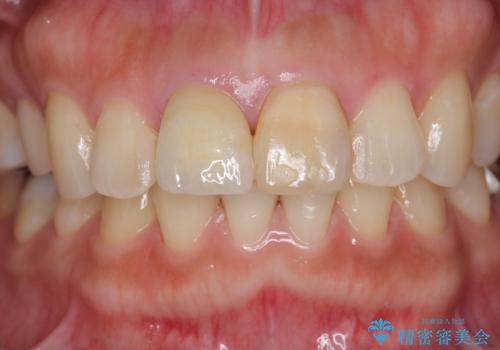

天然歯を再現したリアルな仕上がりに満足いただくことができました。

オールセラミッククラウン スペシャルプランは細やかな色調の再現に優れ、目立つ前歯の審美的な仕上がりがより達成されやすいプランです。